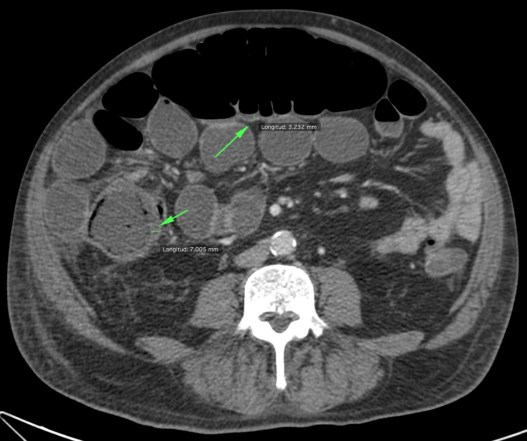

Se realiza TC de abdomen en vacío y con contraste en fase portal:

Estamos ante un cuadro de isquemia intestinal en un paciente con bajo gasto cardiaco con afectación principal de asas intestino delgado, territorio vacularizado por la arteria mesentérica superior.